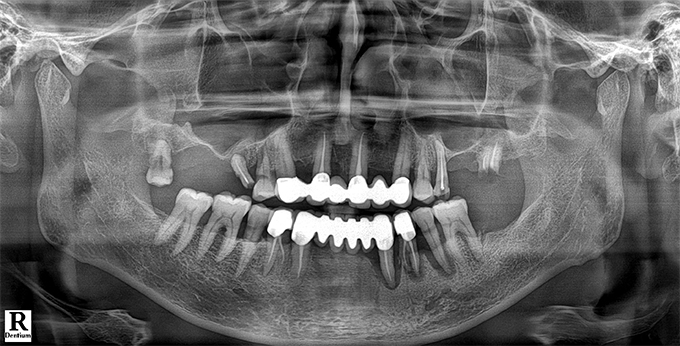

Before & After

임플란트 전후사진

before

2022.11.24

After

2022.12.09

※ 상기 치료전후 사진은 환자의 동의 하에 게재되는 것이며 동일한 촬영각도로 촬영 하였고 치료 기간을 명시하였습니다.

이러한 치료의 결과는 이 환자분에게만 해당되는 것이며 환자의 상태에 따라 똑같은 결과를 얻지 못할 수도 있습니다.

환자분의 상태에 따라 치료 기간, 효과 및 부작용은 상이할 수 있습니다.

치료전후 사진 게재는 의료법 제 23조, 제56조에 의거하여 게재합니다.